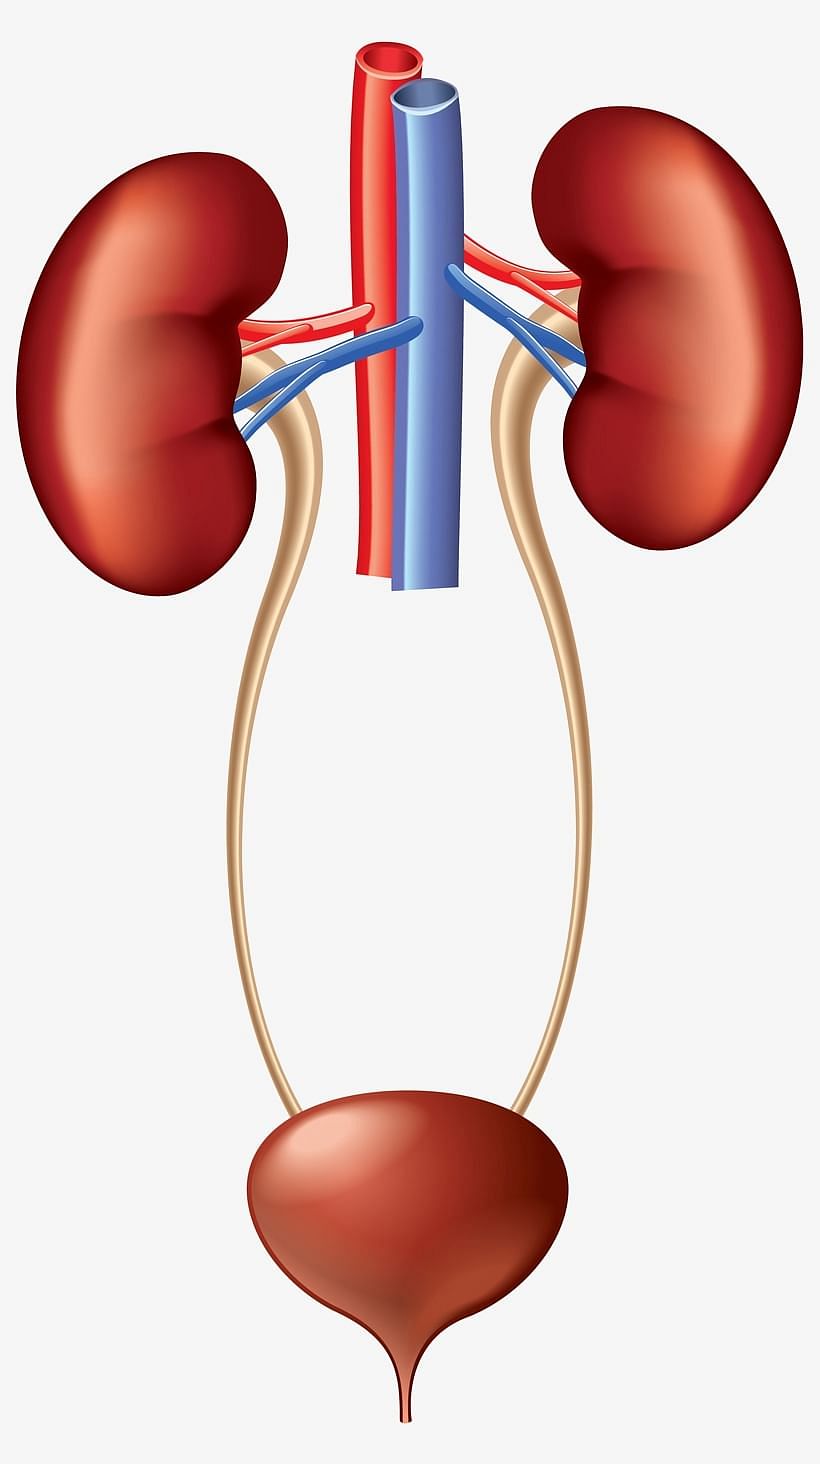

The Excretory System

Excretory System

Excretory System

The organs that remove waste like urine, carbon dioxide, sweat etc. produced in the body form the excretory system.

- As the body parts do their work, waste materials are produced. For example, when food is converted into energy, a gas called carbon dioxide is produced.

- The main organ of this system is a pair of kidneys. The lungs and the skin also help in removing wastes from the body.

- The kidneys expel out urine from the body. The lungs get rid of carbon dioxide. The skin gets rid of sweat.